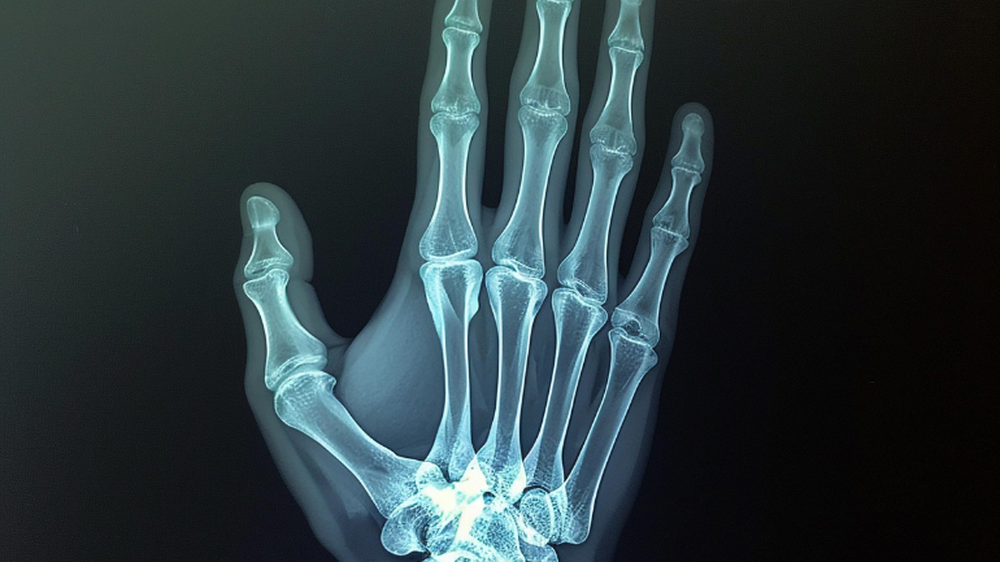

"Abrió la placa, la miró 2 segundos y me dijo: 'Cuándo te quebraste?'. Mi cara fue un poema. Después agregó: 'Sí, mira (dio vuelta el monitor para mostrarme la imagen), este hueso está roto'", relató.

Tras esto, el experto le comentó que si la hubiese visto "el día de la placa", hoy podría estar "casi" recuperada por completo.